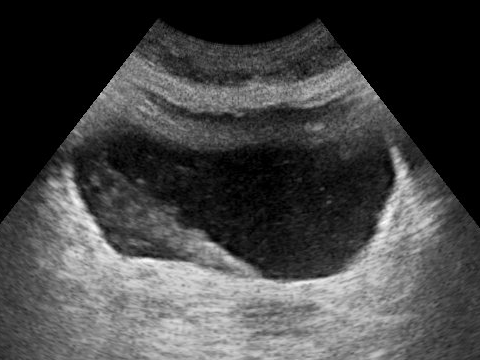

수뇨관과 요로를 보기 위해 여러 형태의 의료 영상 기술이 사용된다.[22] 초음파 검사는 신장과 신우의 수신증으로 인해 막힘의 증거를 보여줄 수 있다.[22] 수뇨관을 더 잘 보여주기 위해 조영제를 정맥 내로 주사하는 것을 포함한 CT 스캔과, 병변을 더 잘 보여주기 위해 조영제를 사용하는 CT 스캔은 양성 병변과 악성 병변을 구별하는 데 사용된다.[22] 조영제를 수뇨관이나 신장으로 직접 주사할 수도 있는데, 전방성 신우 조영술은 조영제를 신우에 직접 주사하는 것이고, 역행성 신우 조영술은 카테터를 통해 요로에 조영제를 주입하여 수뇨관으로 역류시키는 것이다.[22] 더 침습적인 영상 기술로는 유연한 내시경을 요로에 삽입하여 수뇨관을 관찰하는 요관경 검사가 있다.[23] 요관경 검사는 덜 침습적인 제거 방법을 사용할 수 없을 때 중/대형 결석에 가장 일반적으로 사용된다.[23]